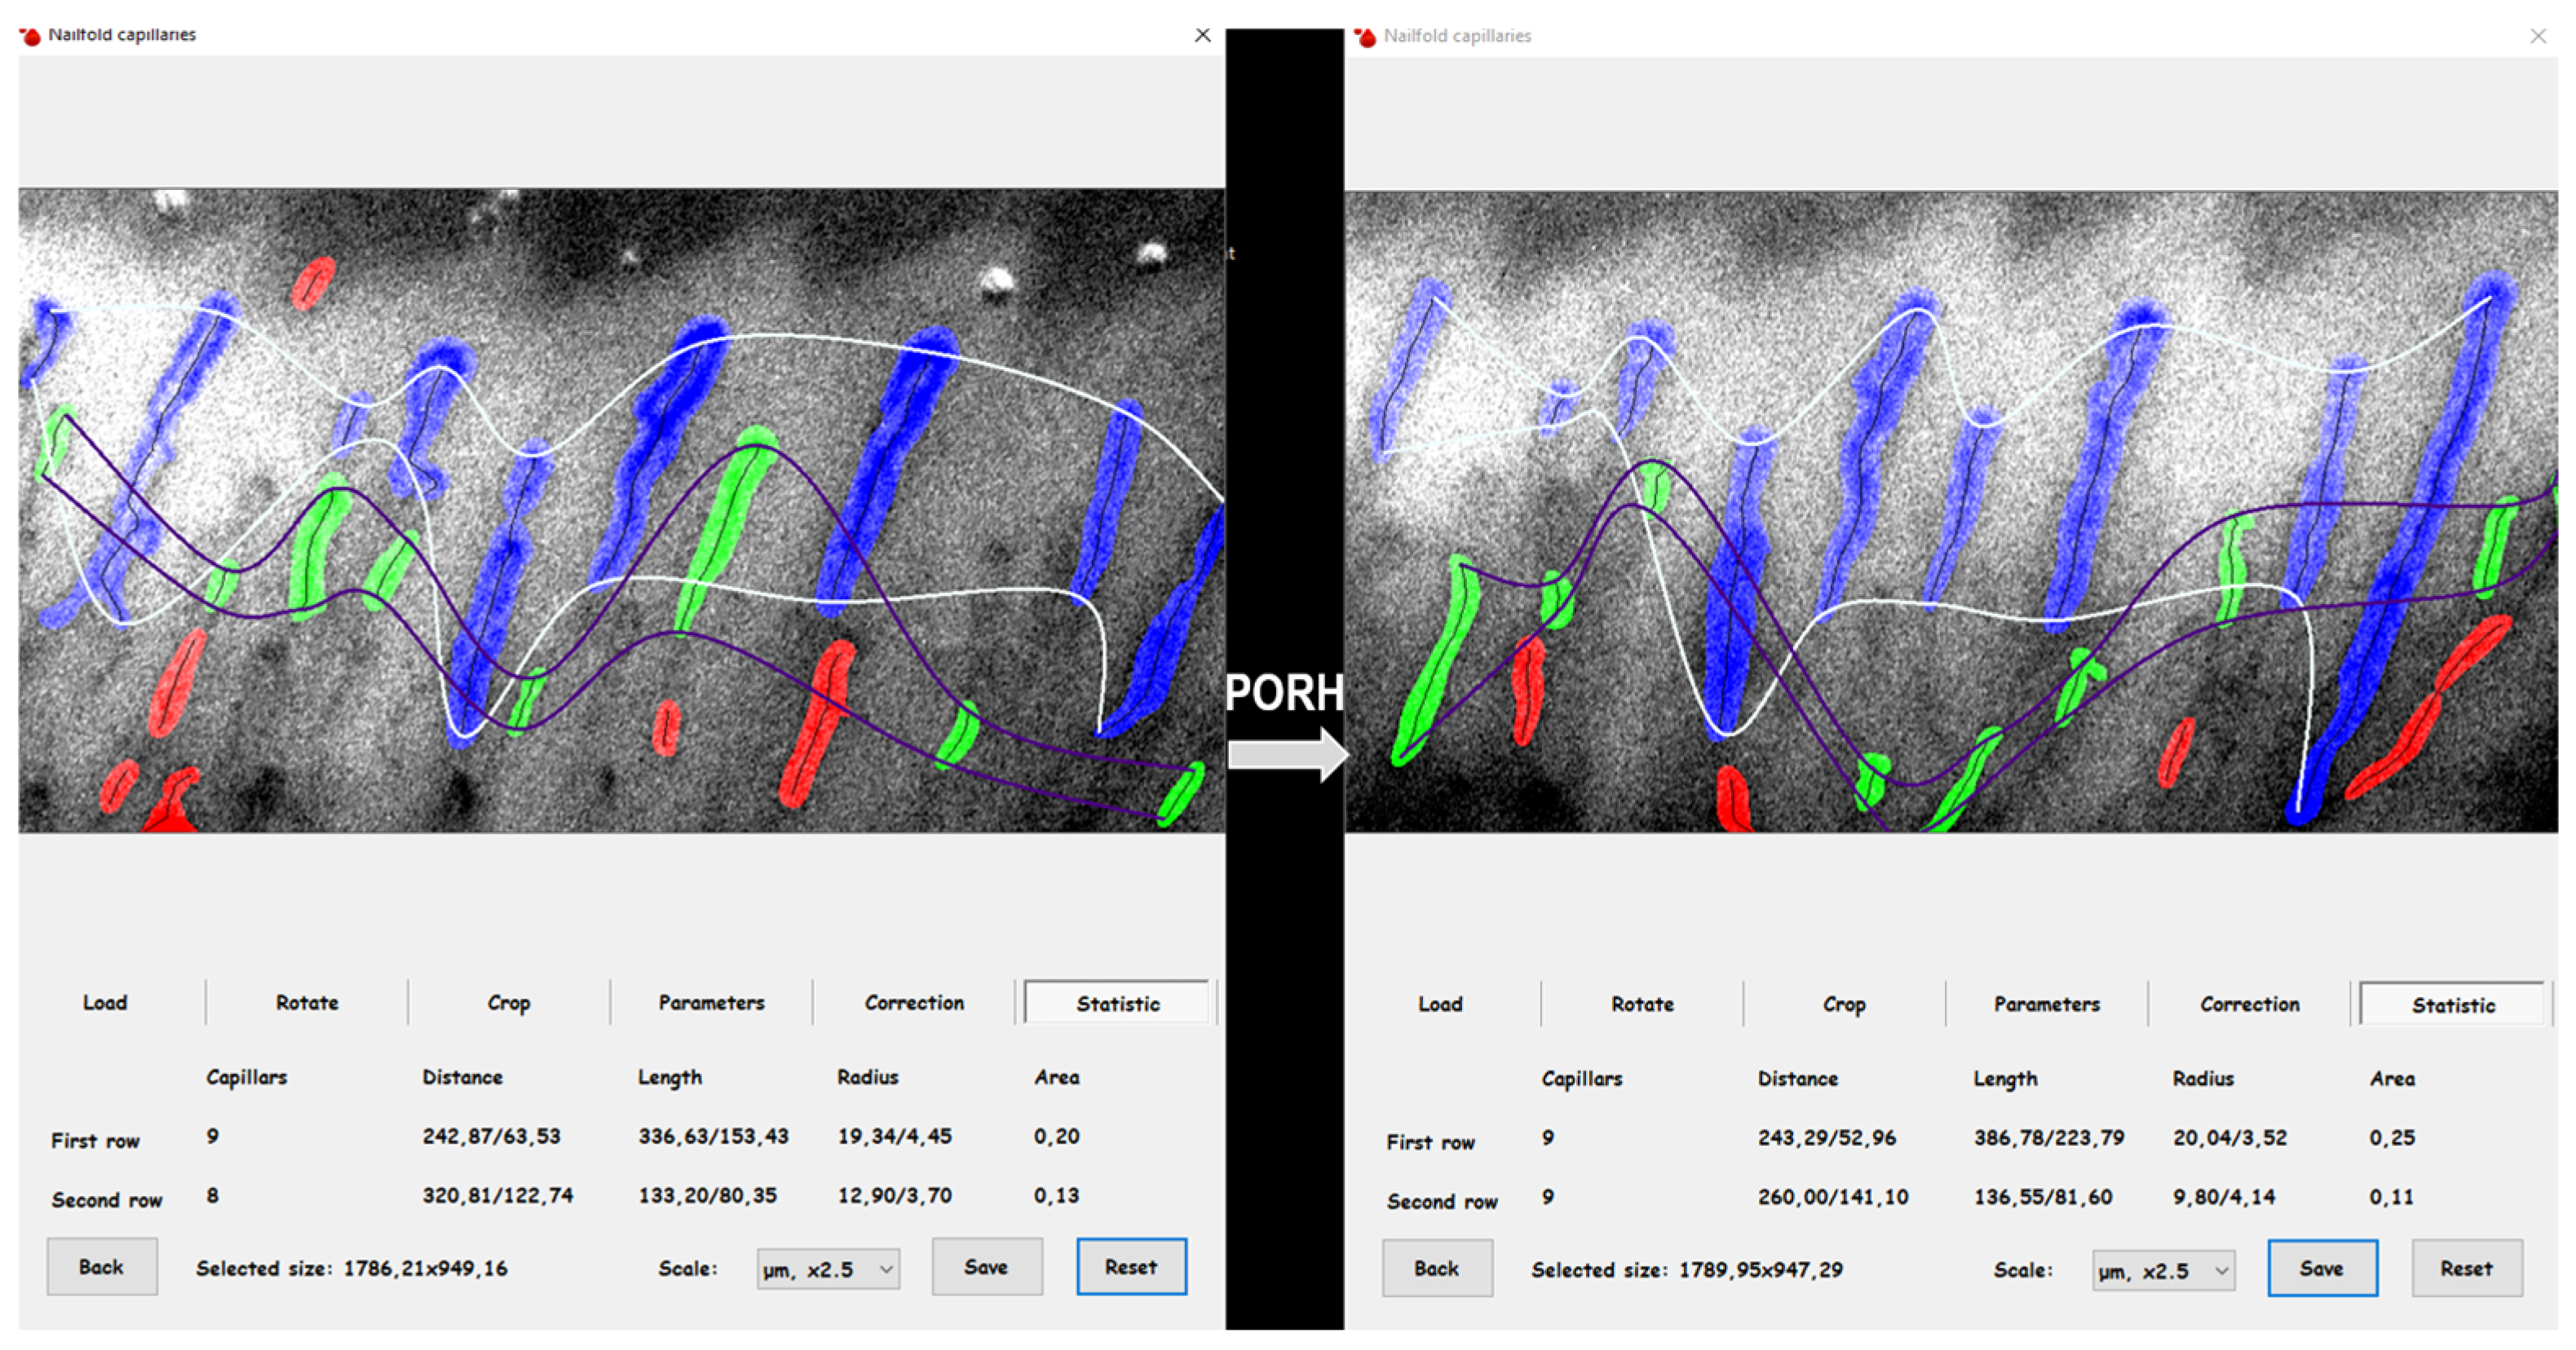

| PORH | post-reactive hyperemia |

| CoverageBASE | ratio of the capillary area to the total area of the determined rows in the baseline condition |

| CoveragePORH | ratio of the capillary area to the total area of the determined rows after PORH |

| ∆CoveragePB | CoveragePORH–CoverageBASE |

| Capillary reactivity | ∆CoveragePB/CoverageBASE |

| DistanceBASE | mean distance between successive capillaries in baseline condition |

| DistancePORH | average distance between successive capillaries after PORH |

| ∆DistancePB | DistancePORH–DistanceBASE |

| Capillaroscopy | |||

| CoverageBASE [%] | 18 (15.3–21) 3.0 # | 15 (12.9–25) 3.1 # | * |

| CoveragePORH [%] | 17 (14.8–21) | 16 (10.3–24) | 0.57 |

| ∆CoveragePB [%] | −1 (−3.1–3) | 1 (−8.1–5) | 0.28 |

| Capillary reactivity | −5 (−16.4–18) | 5 (−41–31) | 0.38 |

| DistanceBASE [µm] | 214.4 (194.5–263.8) 25.4 # | 246.5 (179.4–274.9) 31.3 # | * |

| DistancePORH [µm] | 217.6 (195.4–274.5) | 241.2 (190.2–345) | 0.08 |

| ∆DistancePB [µm] | 2.8 (−32.8–51.7) | 9.7 (−51.5–105.8) | 0.86 |